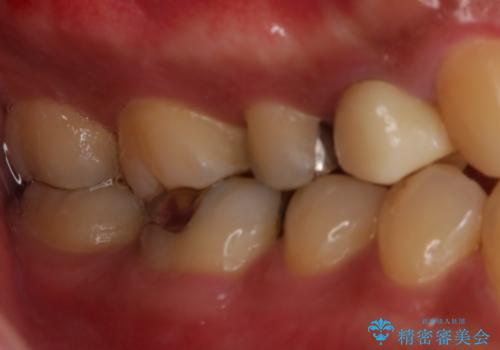

- セラミックへのやり替えを希望された患者様です。

日常的に食いしばる癖があり、歯の表面にはエナメルクラック(歯の表面にできる細かい破折線)も複数認められたため、セラミッククラウンによる治療をご提案しました。